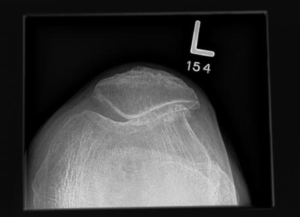

Tibial Tuberosity Transfer (TTT)